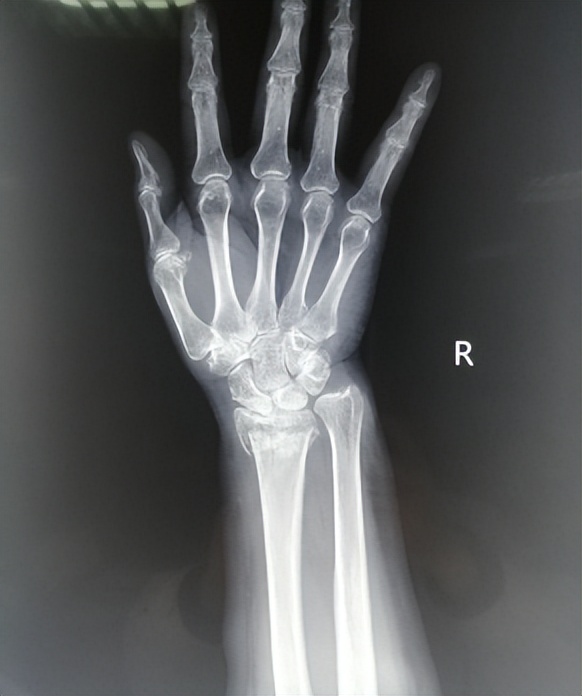

桡骨远端骨折是指距离手腕三厘米以内区域的骨折,此区域是解剖薄弱处,骨质较薄弱,当人体失去平衡摔倒时,手掌撑地易造成该部位骨折。

术后应根据 骨折愈合周期,结合X光片 等进行科学的康复,恢复手和前臂功能。

参考骨折愈合的过程,结合临床,我们把桡骨远端骨折康复大致分为 四个阶段 :